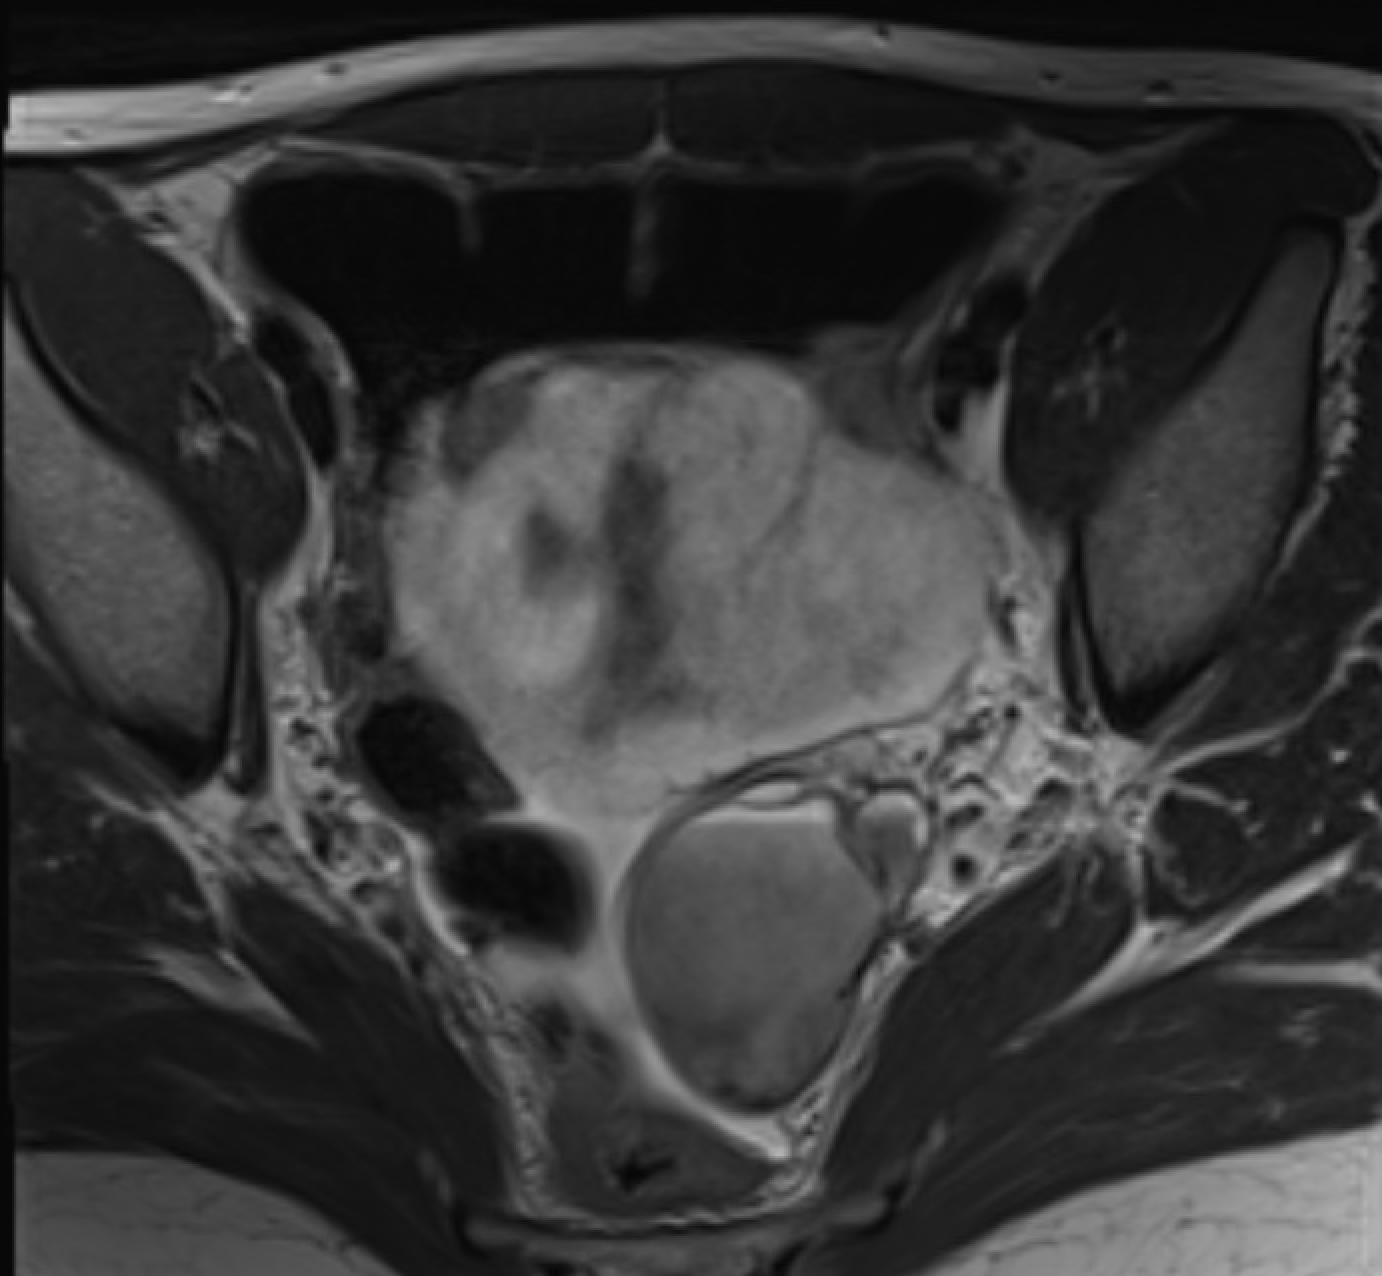

Endometriotic cyst Radiology Cases

From radiologycases.my

Endometriotic cyst Radiology Cases Can You See Endometriosis On A Ct Scan With Contrast Can endometriosis be seen on imaging? Ct scanning typically is not performed in the radiologic evaluation of endometriosis because the appearance of. Systematic approach to sonographic evaluation of the pelvis in women with suspected endometriosis, including terms,. The vast majority of endometriosis is superficial. Unfortunately, most of the time, no. Your doctor may order imaging tests, such as ultrasound, mri,. Can You See Endometriosis On A Ct Scan With Contrast.